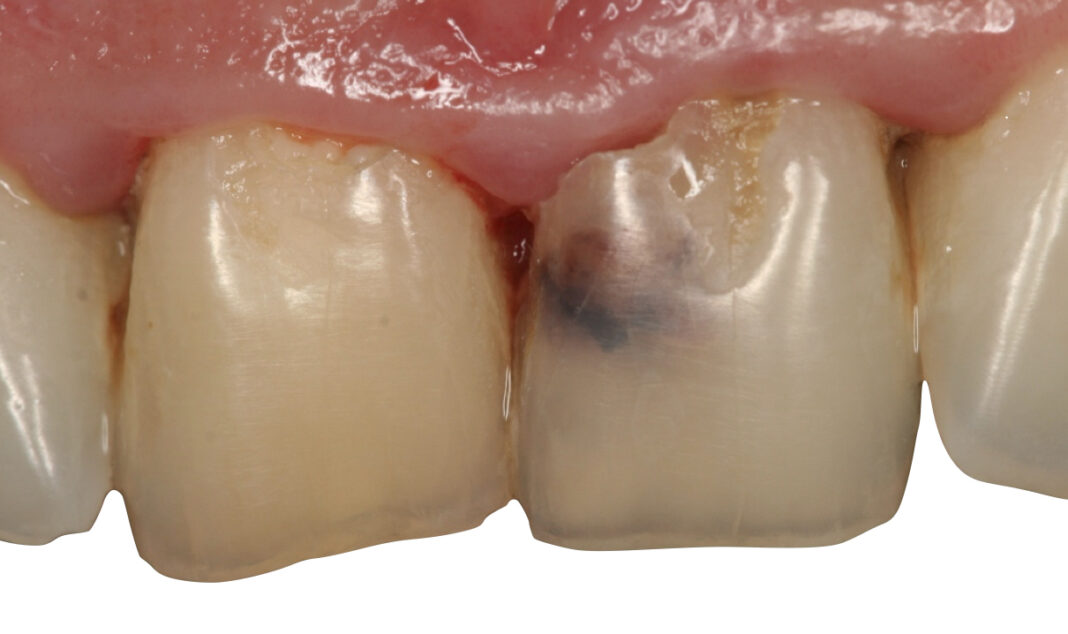

«Il riassorbimento radicolare è una patologia subdola, spesso asintomatica e difficile da diagnosticare, poiché talvolta viene confusa con processi cariosi e, quindi, sottovalutata», prosegue Fornara. Diversi fattori possono danneggiare lo strato predentinale, come i traumi dentari – i più frequenti – l’infiammazione cronica della polpa, le infezioni pulpari subcliniche dovute a processi cariosi o al calore eccessivo durante le fasi di trattamento conservativo/protesico, ma anche stimoli iatrogeni (ortodonzia, sbiancamenti) e procedure pulpari parziali (incappucciamenti, rizotomie in denti vitali eccetera). In generale, i riassorbimenti possono essere causati da traumi, infezioni o trattamenti ortodontici, e, più raramente, da cause sistemiche o idiopatiche».

L’approccio ideale ai riassorbimenti patologici cervicali

Tra le sottocategorie ordinate in base all’eziopatogenesi (riassorbimento superficiale esterno, esterno infiammatorio, sostitutivo interno o esterno, ecc.) vi è il riassorbimento cervicale esterno (RCE), che si sviluppa nella zona cervicale del dente, al di sotto dell’attacco epiteliale, spiega Fornara. «Nei casi di diagnosi tardiva, il riassorbimento può raggiungere il terzo medio o apicale della radice, rendendo vano ogni tentativo di trattamento per recuperare il dente. Purtroppo, nelle fasi iniziali è spesso asintomatico, il che ne complica la diagnosi e riduce le possibilità terapeutiche.

Per il paziente, invece, il riassorbimento, proprio perché spesso asintomatico, ha un impatto emotivo rilevante quando accertato. Se si manifesta con sintomi, può comportare dolore, alterazioni estetiche e compromissione funzionale. L’aspetto più difficile da accettare è che un dente apparentemente sano o correttamente trattato possa andare incontro a una distruzione tissutale progressiva e irreversibile oppure richiedere trattamenti complessi o, in ultima istanza, l’estrazione».